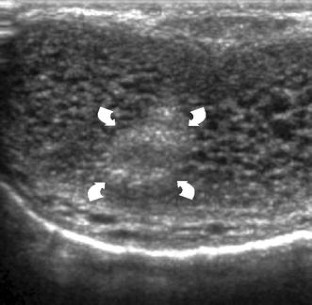

Injury to the penis may result from penetrating or nonpenetrating trauma. Nonpenetrating injury to the erect penis can produce albugineal tear, intracavernous hematoma or extraalbugineal hematoma from rupture of the dorsal vessels. Nonpenetrating injury to the flaccid penis usually follows blunt perineal traumas producing extratunical or cavernosal haematomas, or cavernosal artery tear followed by high flow priapism. Differential diagnosis between albugineal tear and other penile injuries must be obtained as soon as possible, since early surgical repair of albugineal tear reduces significantly the rate of postraumatic curvature and fibrosis. Ultrasonography (US) is able to detect the exact site of the tear in most patients as an interruption of the thin echogenic line of the tunica albuginea. Other imaging techniques are rarely required in the clinical practice. Color Doppler US is the imaging modality of choice to evaluate patients with high flow priapism. Focal or diffuse cavernosal fibrosis can be identified with US as echogenic areas in the cavernosal bodies. Postraumatic erectile dysfunction can result from fibrotic changes, nerve and vascular impairment or both. Doppler evaluation of penile vasculature is required in young patients with postraumatic impotence before surgical revascularization procedures.

Fig. 5

Fig. 6